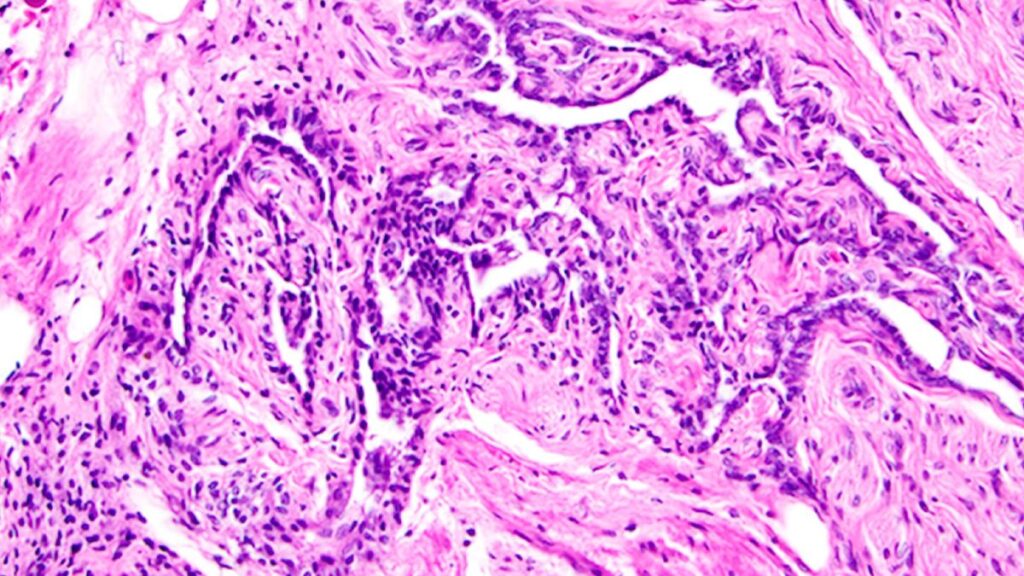

Longtemps considéré comme inutile, cet organe du corps féminin est en réalité essentiel

Le rete ovarii est une structure mal comprise du corps féminin. Reliée aux ovaires, elle pourrait être beaucoup plus essentielle à la fonction ovarienne et à la fertilité que les scientifiques ne le pensaient jusqu'à présent. The post Longtemps considéré comme inutile, cet organe du corps féminin est en réalité essentiel appeared first on Daily Geek Show.

Le rete ovarii est une structure mal comprise du corps féminin. Reliée aux ovaires, elle pourrait être beaucoup plus essentielle à la fonction ovarienne et à la fertilité que les scientifiques ne le pensaient jusqu'à présent.